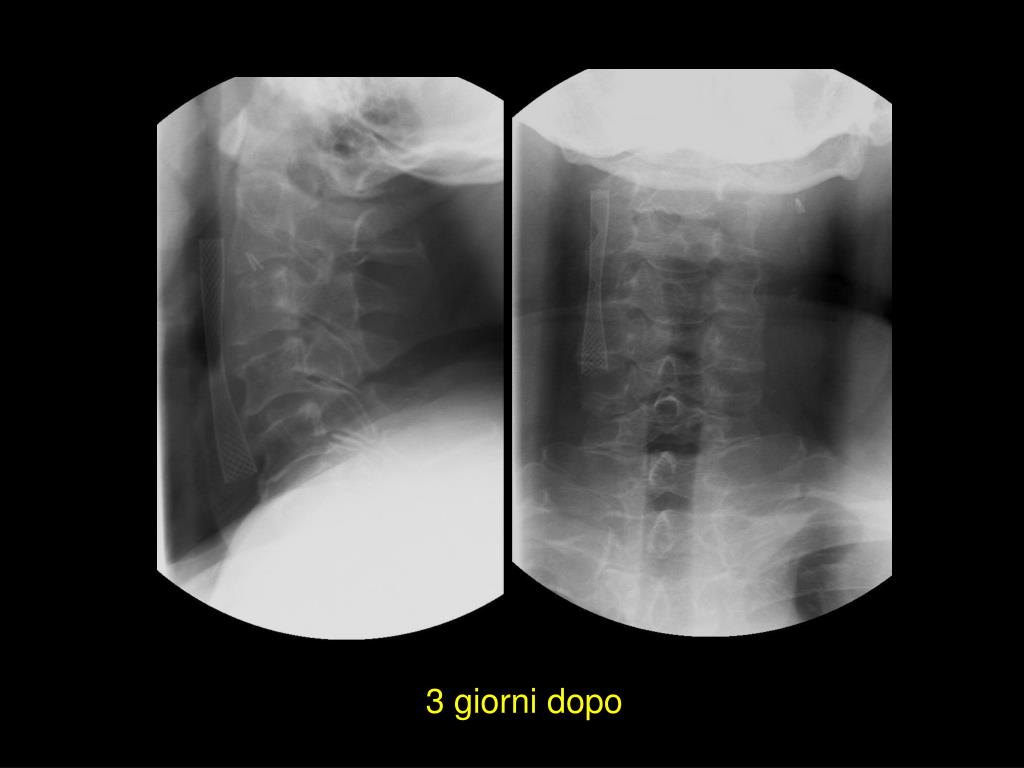

20. 3 giorni dopo il trattamento

26. 3 giorni dopo

28. Caso stenting bilaterale CI destra